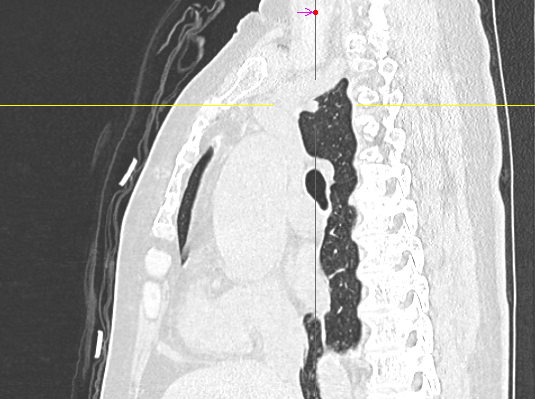

数月前,66岁的龚女士在肺癌术后随访复查中,胸部CT报告显示其右上肺新发实性结节一枚,并由刚开始发现时的5mm逐步增大至10mm。更棘手的是,这个结节位于右肺上叶尖段的纵隔胸膜下,位置极其“刁钻”。面对这份报告,患者龚女士陷入了深深的焦虑。因为其7年前因右中肺肿瘤行右中肺癌根治术,对于新发的实性结节为何种性质,是新发肺恶性肿瘤或是良性病变,亦或是原肺癌复发转移,目前均不能明确。辗转多家医院,得到的建议多为“定期观察,等待变化”或考虑创伤较大的传统穿刺活检,但结节位置非常深,单纯CT引导下定位穿刺很难精准到达,且需穿行的肺组织较多,创伤较大。

胸外科马海涛主任团队对龚女士的病情进行了深入细致的评估:结节虽小,但形态学特征具有风险,且结节逐步增大,结合既往肺癌病史,考虑肿瘤复发可能,“定期观察”方案会让患者持续承受心理煎熬。然而,传统的CT引导下经皮肺穿刺定位,对于如此深部、微小的结节,极易导致气胸、出血等并发症,风险极高。

定位完成后,手术进入第二阶段。团队并未在患者胸部留下多个孔洞,而是仅在其肋间开创了一个长约3厘米的单一操作孔。通过这个“钥匙孔”,高清荧光胸腔镜顺利进入。在之前定位的明确指引下,手术团队迅速而准确地找到了这个深藏不露的结节,精准实施了“肺叶部分切除术”。

马主任解释系统原理:“这套系统就像为我们医生的操作装上了‘肺部GPS’。它通过术前将患者的CT影像数据导入系统,构建出独一无二的肺部三维‘地图’。术中,在磁场的引导下,我们操控一根细如发丝的导航探头,经由患者的口腔、气管这一自然通道,毫无创伤地直达常规支气管镜无法到达的肺外周深处,精准地停靠在目标结节旁边。磁导航支气管镜的优势是决定性的。它实现了‘经自然腔道、无创抵达’,彻底避免了经皮穿刺可能引起的高达20%-30%的气胸风险,为定位深部结节提供了安全、精准的解决方案。”